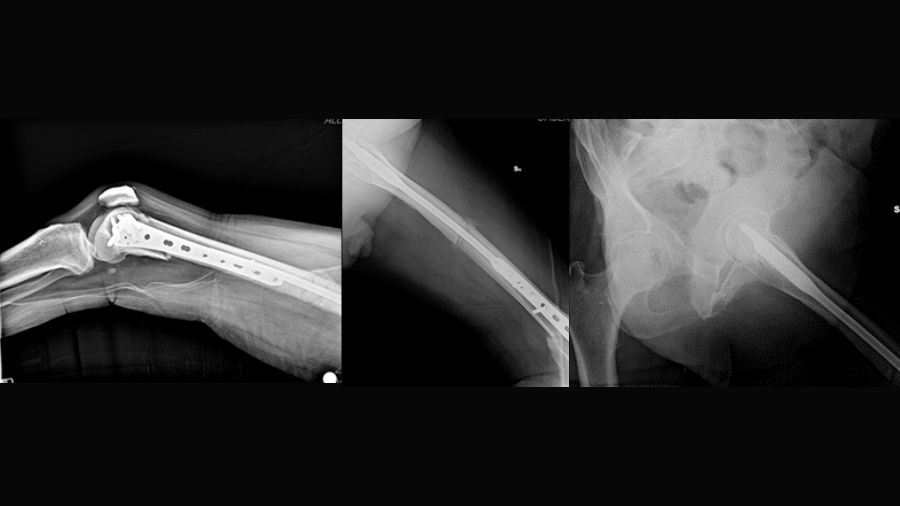

The trifocal femoral fracture (Figure 1) was classified as an obliquely oriented transcervical femoral neck fracture (AO/OTA 31-B2), a displaced shaft fracture (AO/OTA 32-A2), and a supracondylar fracture with intra-articular extension (AO/OTA 33-C2).